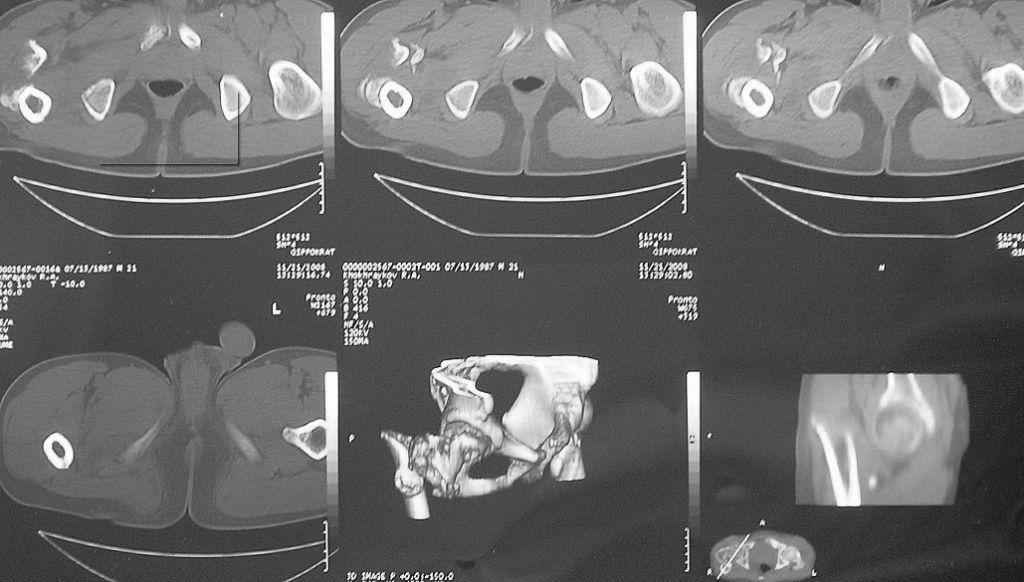

Leonid Solomin 03 Март 2009, 22:07

Уважаемый Попов Виктор!

Возможно, пример (в приложении) поможет Вам определиться с выбором тактики лечения (у нашего пациента, кроме тугого ложного сустава вертельной области, сложная деформация н/3 бедренной кости; т.к. это не имеет значения к обсуждаемой теме - оставил "за кадром"). Как Вы видите, мы в данном случае не вводили чрескостные элементы в зону установки имплантата. При отказе от наложения опоры на таз (кстати, она не обязательно может быть громоздкая спицевая; арки со стержнями-шурупами, введенными в крыло подвздошной вполне достаточно) "не удивляйтесь", если опора со стержнями-шурупами, введенными в вертельной области в скором времени дестабилизируется, возникнет воспаление мягких тканей у чрескостных элементов. Такая опора "имеет на это право": нагрузка конечности от вершины дистального фрагмента до кончиков пальцев ляжет на нее. А двух-трех введенных рядом стержней-шурупов, как их не разноси от фронтальной плоскости, в данном

случае явно недостаточно для адекватной фиксации. + для того, чтобы выбрать оптимальные чрескостные элементы для промежуточной и дистальной опор, можете воспользоваться атласом

В приложении пример пациента, близкого по картине к тому, что представил Виктор (варус и смещение периферического отломка на поперечник кзади). Сделали как раз то, что Виктор исходно намеревался - аппаратная коррекция и затем гамма.